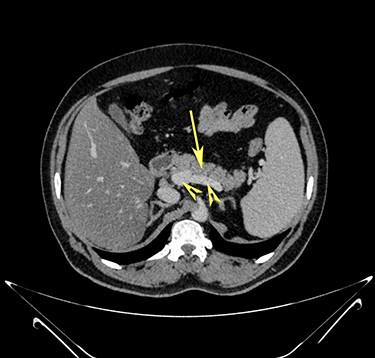

Computerized tomography showed a solitary well defined intraperitoneal cyst consisting of fluid showing low attenuation. The wall of the cyst was 1 cm thick, with no contrast enhancement. It was situated in the pelvis compressing the urinary bladder. It had no communication with either the bowel or the urinary bladder. The pancreas was normal, as also the rest of the abdominal organs. There was no ascites (Figs. 1–5). The diagnosis was a large intraperitoneal infected cyst.

Transverse section image of a contrast-enhanced CT scan of the abdomen at the level 4–4 (Fig. 1), showing a solitary cyst (C) with a non-enhancing wall separate from the urinary bladder (B). Iliac vessels are labelled with arrowheads.